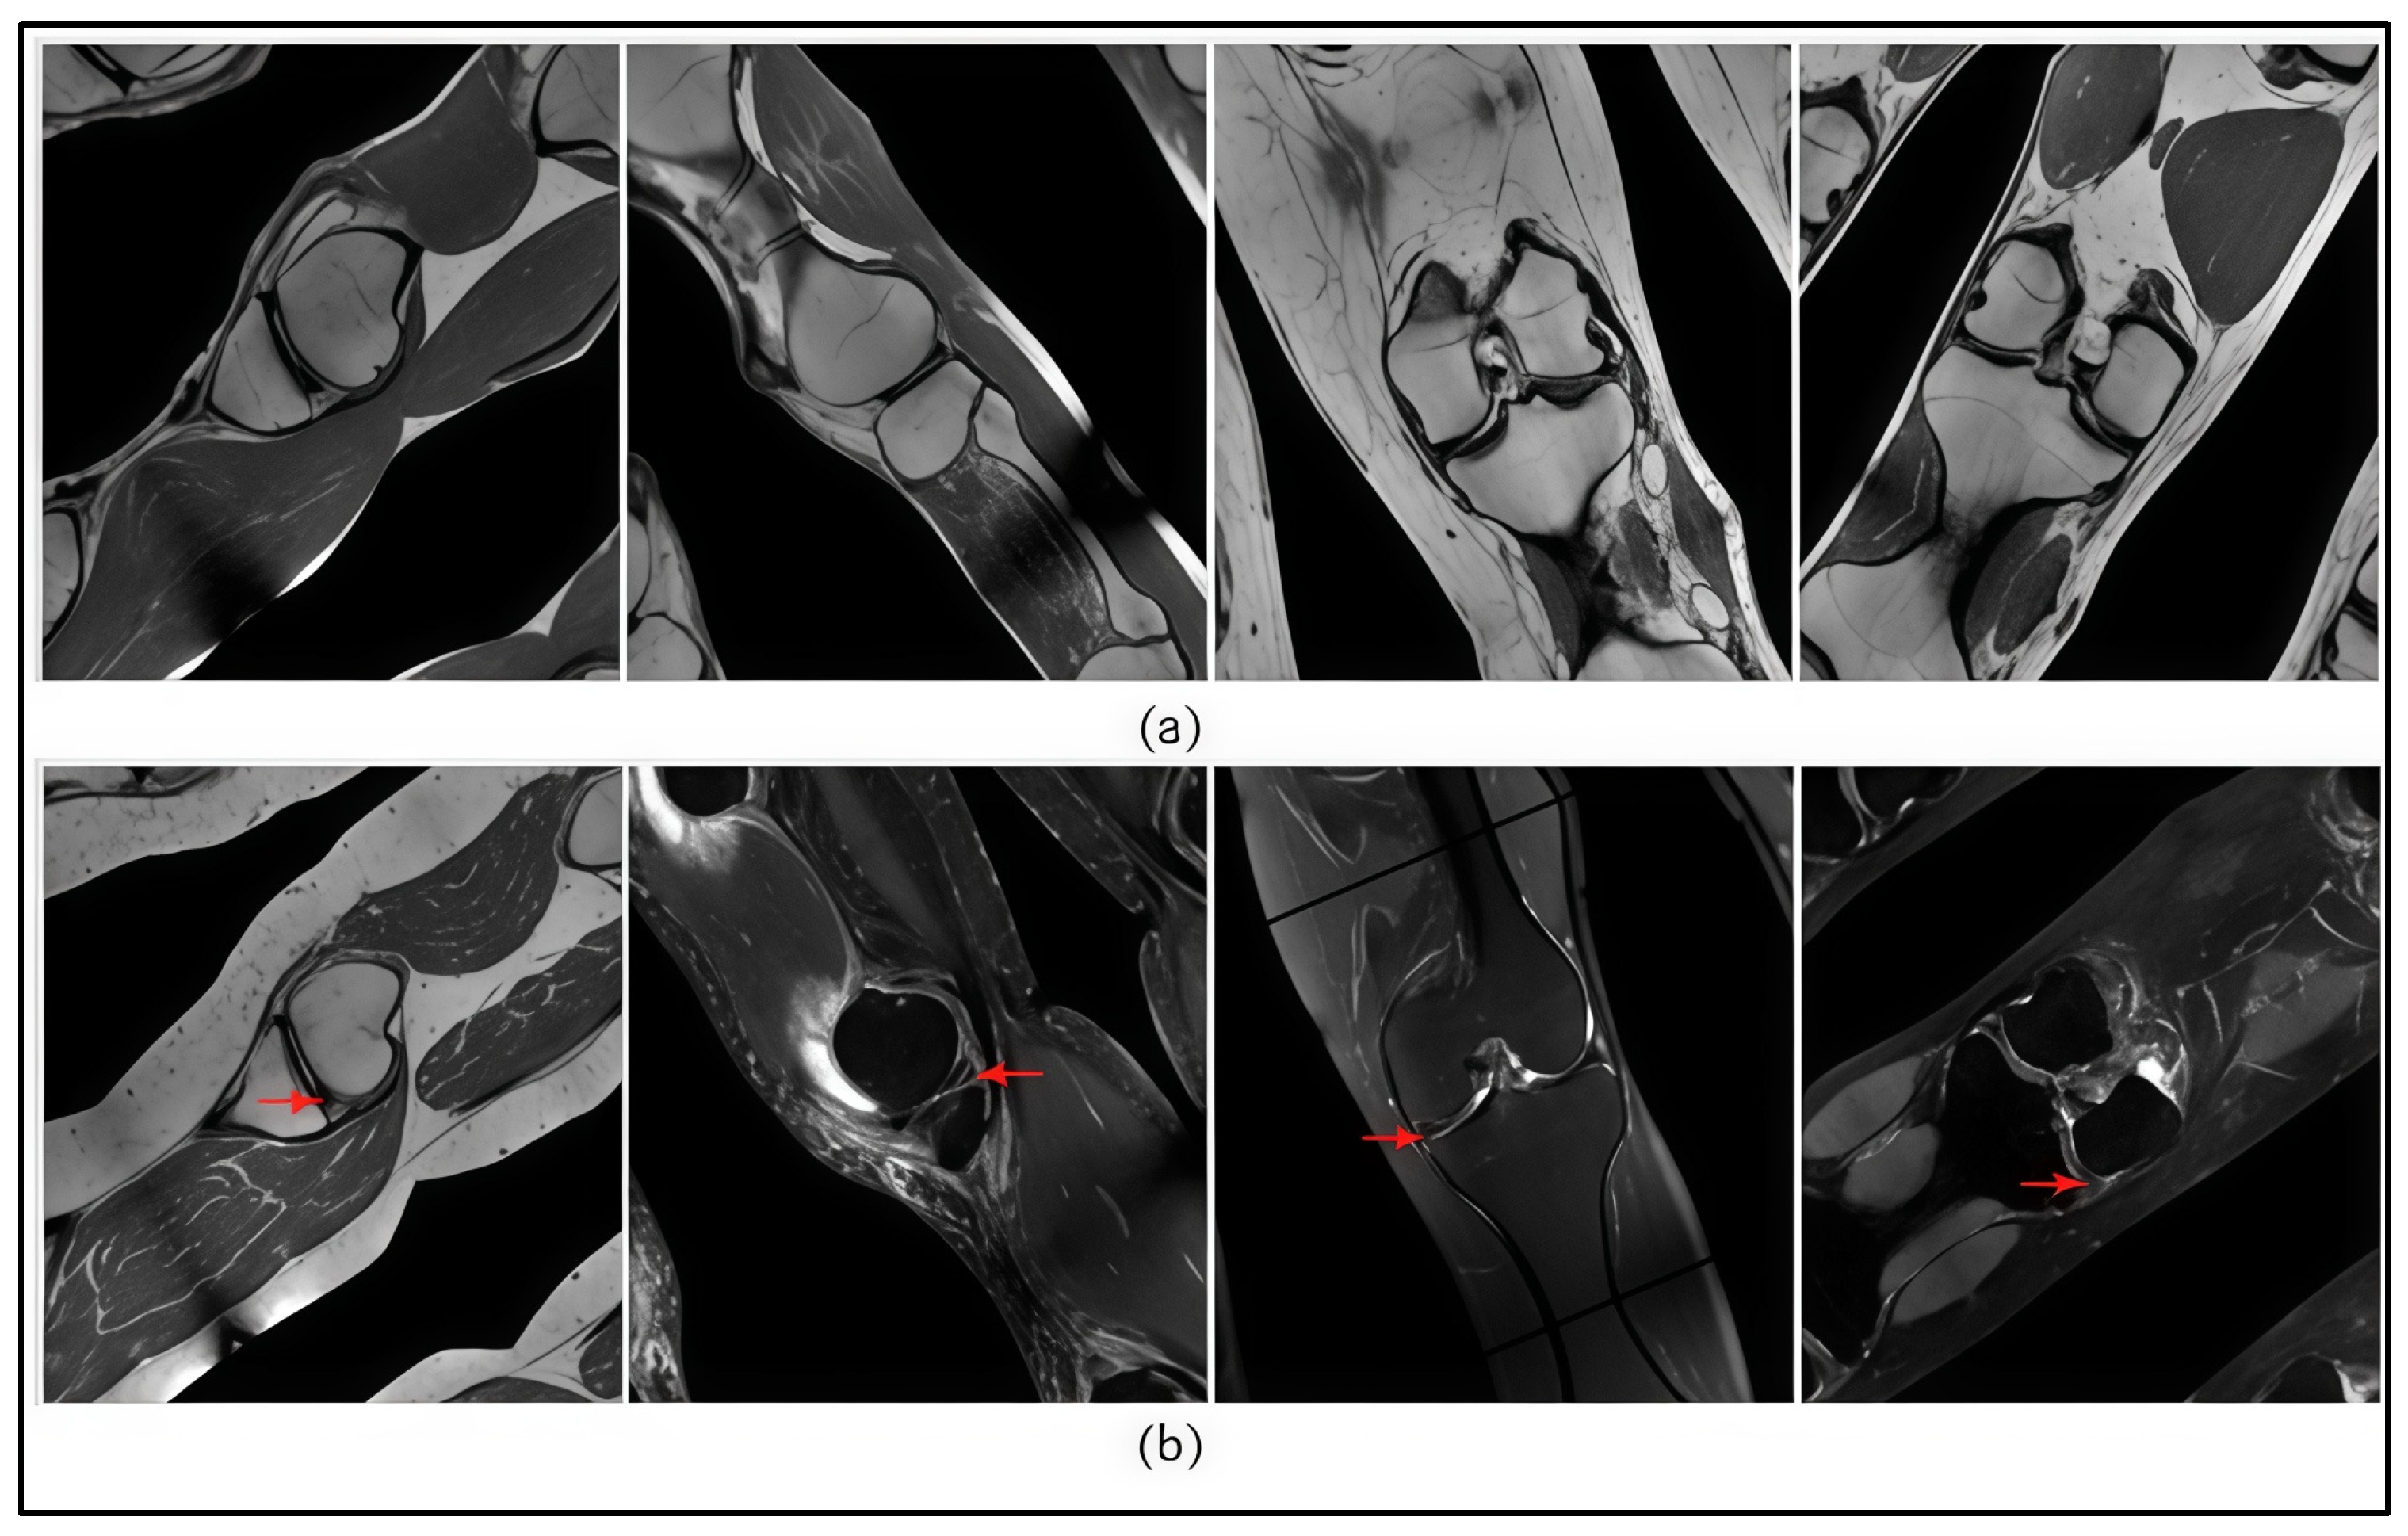

During the data preparation phase, all images were manually annotated and categorized into two classes: 0—images without a meniscal tear; 1—images with a confirmed meniscal tear. Representative examples from the dataset are shown in Figure 2.

Figure 2.

(a) Images without a meniscus tear (class 0); (b) images with a confirmed meniscus tear (class 1). Arrows indicate the site of the meniscus tear.

The data labelling was performed in a stepwise manner. A total of 4262 images were initially distributed. The images selected during the labelling phase were reviewed by an expert. Following verification, the final number of labelled MRI images was 2000, with a total of 7990 annotated objects. Table 1 presents the distribution of images and objects by class.